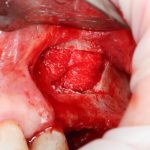

Возвращаемся к основной операционной области. Еще раз посмотрим на альвеолярный гребень, поофигеваем от его ширины и моих грандиозных планов:

На этом месте мне следует дать некоторые пояснения.

Если ты читал мои предыдущие публикации, посвященные остеопластике, то наверняка знаешь, что костное ложе перед фиксацией графта (любого графта) требует некоторой подготовки. В основном она заключается в полном или частичном удалении кортикального слоя и, применительно к АТККФ — адаптации не только блока под ложе, но и ложа под пересаживаемый костный блок. Подробности здесь>>

Ежу понятно, что к необходимости этих манипуляций мы пришли не сразу. А тогда был 2013 год… и у меня были мысли, что подготовка костного ложа нужна не всегда и не всем. Здесь я понадеялся на размер костного дефекта и большую площадь контакта между костным аутотрансплантатом и принимающим ложем. Конечно, сейчас я сделал бы немного по-другому.

Я зафиксировал костный блок практически без адаптации на несколько винтов. Обрати внимание, что винты находятся в зоне, где не планируется установка имплантатов. Фиксация должна быть надежной, поскольку мне еще предстояла подготовка лунок для имплантатов. Трех винтов для этого вполне достаточно.